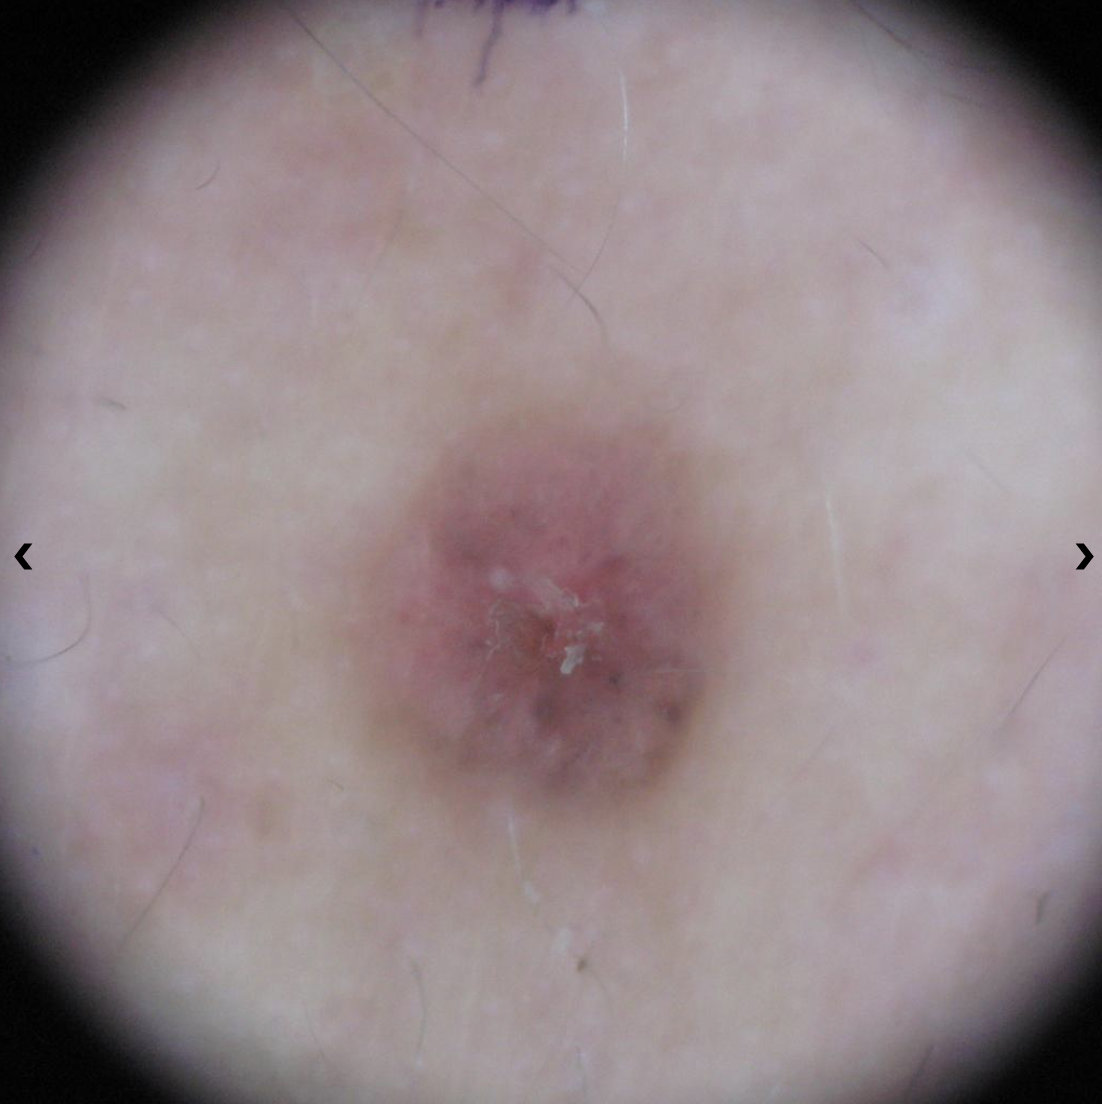

Basal Cell Carcinoma (BCC) Photos

Basal cell carcinoma on the posterior torso. Photo: International Skin Imaging Collaboration at isic-archive.com

Basal cell carcinoma on the neck. Photo: International Skin Imaging Collaboration at isic-archive.com

Basal cell carcinoma on the anterior torso. Photo: International Skin Imaging Collaboration at isic-archive.com